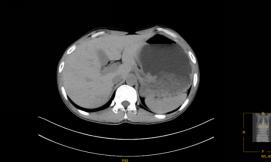

CT检查提示胃腔内大量胃内容物残留,提示胃潴留